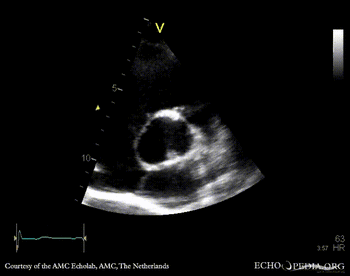

E00341.gif E00342.gif

A5CH: Color Doppler, moderate aortic regurgitation PSAX: bicuspid aortic valve